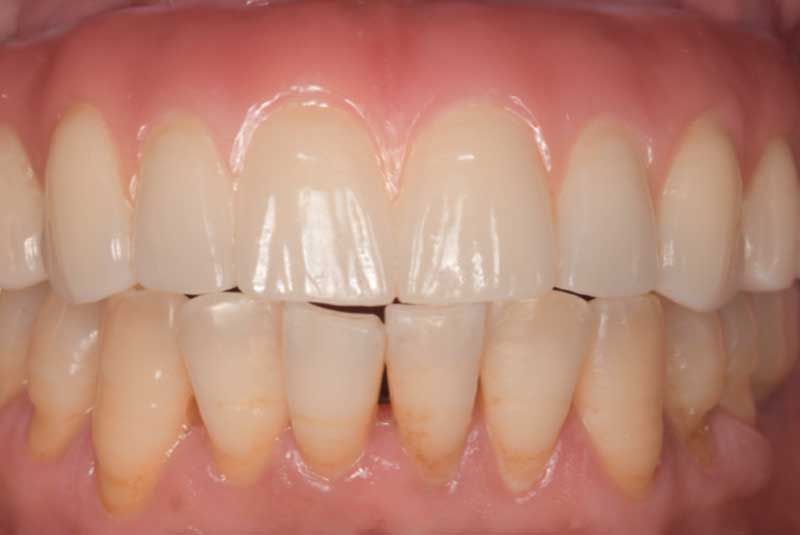

Before & After Crowns (#6,7,8,9,10,11,22,23,24,25,26,27), Overlay (#3,4,13,14,21,28,29), Implant & Implant Crowns (#5,12,19,20,30)